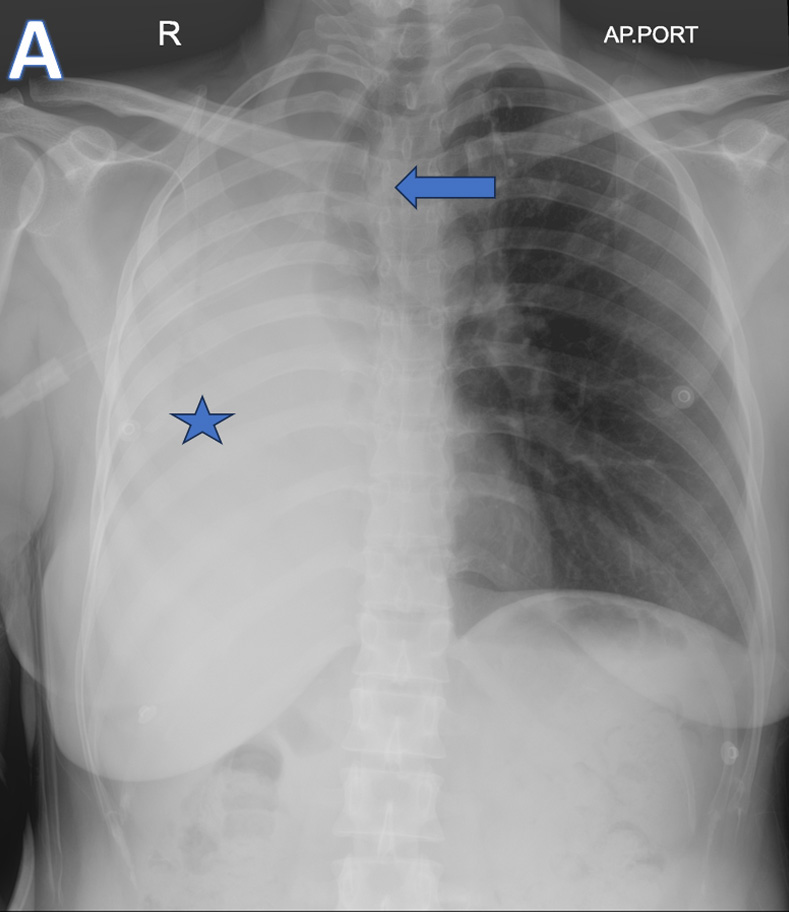

B – Axial CT thorax (soft tissue and lung window images)

• ARROW: Soft tissue density endobronchial mass lesion in the right main bronchus.

• STAR: Collapsed right lung and hypodense  fluid in the right hemithorax.